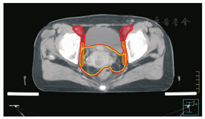

笔者所在科室对于FIGO临床分期为ⅡB期宫颈癌(阴道穹窿受侵、宫旁受侵近盆壁)的调强放疗流程及靶区CTV勾画范围建议如下。对其定位前准备工作包括:患者于定位前30~40 min排空膀胱,再饮水500 mL(含造影剂碘化醇10 mL),显影小肠。对其靶区CTV勾画具体操作步骤为:让患者取仰卧位,身下垫胸、腹平板,双手抱肘并上抬置于额头,热塑体膜固定(上腹至大腿上约1/3处);待热塑体膜冷却成形后,激光灯下于体前正中和两侧分别置铅点(尽可能靠近靶区中心)。此时尽可能行CT增强扫描,以更清楚显示解剖位置;对造影剂过敏、高龄、伴有严重并发症等不适合行CT增强扫描者,仅进行平扫。CT检查的扫描范围为:第一腰椎体上缘至坐骨结节下2 cm,层厚为5 mm,若腹主动脉旁淋巴结转移,则上移至隔顶;若全阴道浸润、腹股沟淋巴结转移,则下移至外阴下4 cm。其中,对靶区CTV勾画:放疗前,应常规实施CT、MRI或PET-CT检查,以明确肿瘤靶区范围及是否存在远处转移(部分远处转移病变,可与原发部位同时进行放疗)。对于其GTV勾画,则包括临床肉眼可见或可触及的,或可通过检查手段证实的肿瘤区域,具体包括宫颈肿瘤、受侵宫旁及阴道组织。MRI检查是确定软组织及宫旁受侵的较理想方法。若腹膜后淋巴结转移,需对淋巴结照射剂量进行加量时,CTV则应单独勾画转移淋巴结靶区。CTV勾画分为局部肿瘤区域和淋巴引流区域。局部肿瘤区域CTV勾画,包括局部肿瘤GTV及显微镜下可见的亚临床肿瘤病变,首先为宫颈、宫体、宫旁和阴道CTV勾画。①宫颈CTV:勾画全部宫颈。②宫体CTV:勾画全部宫体。③宫旁CTV:勾画上界为乙状结肠跨过子宫及输卵管处,下界为泌尿生殖膈,前界为膀胱后壁/髂外血管后缘。若子宫前倾明显,则子宫前界为宫旁前界,后界为宫骶韧带和直肠系膜前缘,内侧界为子宫颈阴道,外测界为骨盆壁,不包括肌肉和骨。值得注意的是:若宫骶韧带受累,CTV勾画则需将整个宫骶韧带全部包括在内,此时直肠系膜淋巴结及直肠周淋巴结均应包括在内。对于FIGO临床分期为ⅢB期及以上者,CTV应将直肠周淋巴结勾画在内,宫旁靶区与髂淋巴结及闭孔淋巴结区重叠。④阴道CTV:若阴道无受侵,则勾画阴道上段1/2,若上段受侵,则勾画阴道上段2/3,若阴道广泛浸润,则勾画全阴道。其次,盆腔淋巴结引流区包括宫颈旁、宫旁、闭孔、髂内、髂外、骶前及髂总淋巴结CTV勾画,依照其血管走行进行勾画。①髂总动脉CTV:上界为腹主动脉分叉下缘,下界为髂总动脉分叉下缘;前界为血管前7 mm,后界为血管后7 mm;内侧界为血管内侧7 mm,外侧界为血管外7 mm,腰大肌内侧缘,包括腰大肌与椎体旁间隙。②髂外动脉CTV:上界为髂总动脉分叉下缘,下界为股骨头上缘即股动脉;前界为血管前7 mm,后界为血管后7 mm;内侧界为血管内侧7 mm,以子宫、卵巢、肠管、输尿管及膀胱为界,外侧界为血管外7 mm,腰大肌及髂腰肌内侧缘。③髂内动脉CTV:紧邻髂内血管及其分支,上界为髂总动脉分叉下缘,下界为尾骨肌上缘、坐骨棘或子宫动静脉上端;前界为血管外7 mm,后界为上部以骶骨翼为准,中下部至梨状肌前缘或臀下动静脉;内侧界为血管外7 mm,外侧界为头侧髂腰肌、髂肌或骶髂关节外侧,中间为髂骨、髂腰肌或髂肌内侧缘;尾侧界为闭孔内肌或梨状肌内侧。④闭孔淋巴结CTV:上界为骶髂关节下缘连接至髂内淋巴结,下界为闭孔上缘;前界为上中部分连接到髂外,下部至耻骨后缘,后界上中部连接到髂内,下部至闭孔内肌后缘;内侧界至膀胱、子宫及肠管,沿骨盆壁向内扩18 mm,外侧界至闭孔内肌、髂肌、髂腰肌或髂骨。⑤骶前淋巴结CTV:上界为髂总分勾画范围,见图1,图2,图3,图4,图5,图6。